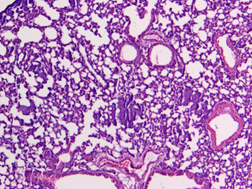

圖1 HE染色圖 40X

樣本中細胞核被蘇木精染成鮮明的藍色。細胞質(zhì)被伊紅染成深淺不同的粉紅色至深紅色。對比鮮明。可以清晰觀察到組織形態(tài),符合HE染色結(jié)果的要求。